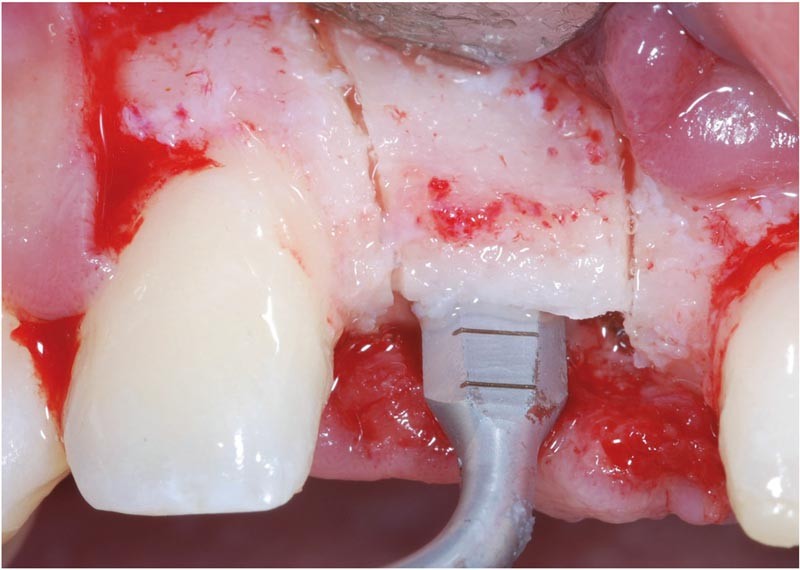

Face à ces situations, la technique d’expansion crestale introduite par Tatum [16], modifiée par Summers [15], puis appliquée en piézo-chirurgie [17] est basée sur le principe de l’élasticité osseuse obtenue par corticotomie. Facilitée par l’utilisation de la piézo-chirurgie, cette technique apparaît comme une solution intéressante pour l’amélioration du volume osseux vestibulo-lingual des crêtes édentées étroites.

Technique

Le principe consiste à réaliser un volet osseux en vestibulaire du site édenté de façon à pouvoir effectuer une expansion de la crête en direction vestibulaire. Une fois cette expansion faite, un forage conventionnel a minima permet la stabilisation primaire de l’implant…